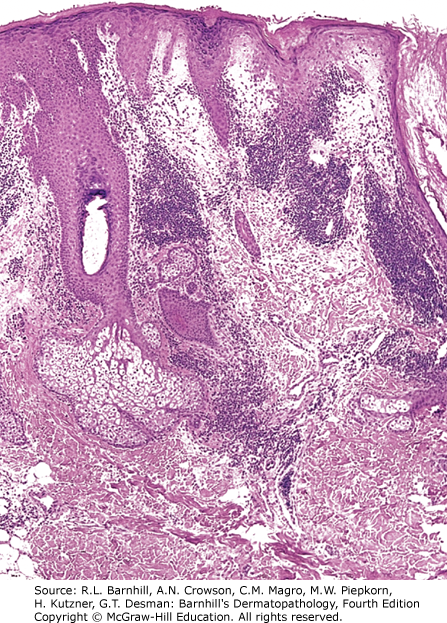

A 60-year-old female patient presents with a pruritic rash on her arm. A biopsy of a lesion shows the following histologic findings.

Which of the following diagnoses is most consistent with the histopathology shown above?

Rationale: Recognizing the type of infiltrate in dermatopathology slides can help categorize rashes and narrow the differential diagnoses. All the answer choices have very different patterns (vascular growth in pyogenic granuloma) and different types of inflammatory infiltrate (neutrophilic, eosinophilic, granulomatous, or lymphocytic). Identifying eosinophils and flame figures in the photographs above is critical to the identification of the correct diagnosis.

The photographs above demonstrate perivascular mixed infiltrate with multiple flame figures. Flame figures represent degranulated eosinophils. Wells syndrome presents clinically as erythematous papules and plaques that can appear similar to cellulitis and are typically pruritic. Flame figures are not pathognomonic for Wells syndrome and can be seen in other eosinophilic processes such as arthropod reaction, allergic contact dermatitis, and bullous pemphigoid. Patients diagnosed with Wells syndrome should be evaluated for underlying malignancy, medication reaction, or parasitic infections.